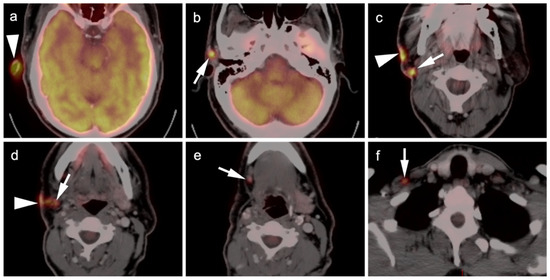

4.5. Pheochromocytoma and Paraganglioma

5. Conclusions